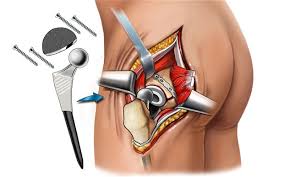

Introduction Hip pain and stiffness can significantly affect mobility and quality of life. Conditions such as osteoarthritis, rheumatoid arthritis, hip fractures, and degenerative joint diseases often lead to chronic...